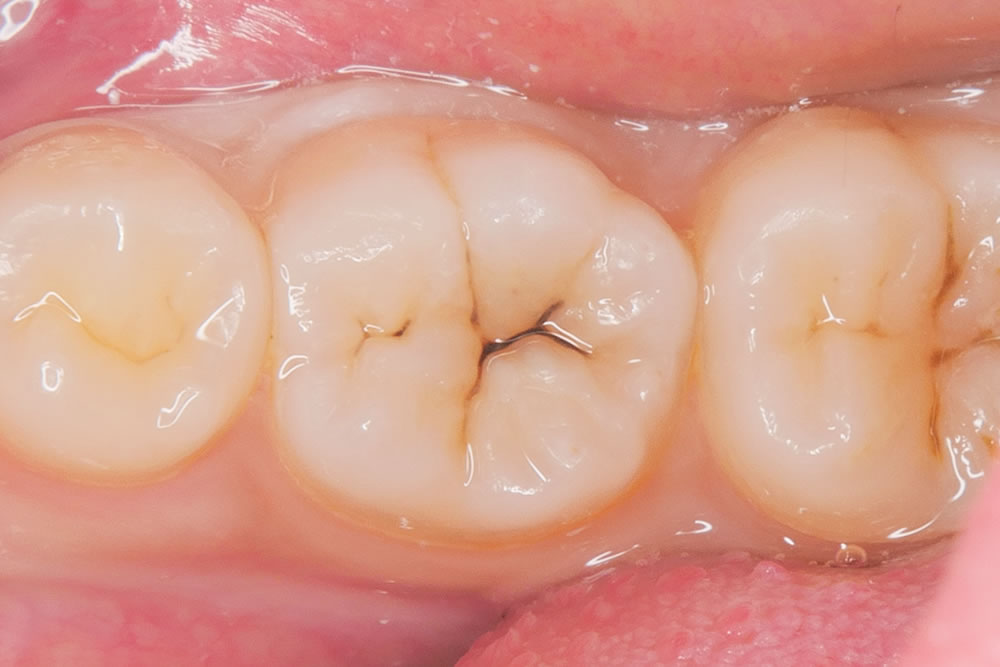

こちらの患者さまは、右下奥歯の虫歯を主訴に来院されました。

右下の奥歯に黒い部分が見受けられます。範囲は小さいため、出来るだけ削らないように先端の小さな器具を用いて丁寧に虫歯を除去していきます。

虫歯治療の除去

う蝕検知液を用いて丁寧に虫歯を取り除いていきます。

さらに奥にある虫歯は、より小さな器具を用いて削る範囲が大きくなりすぎないようにします。